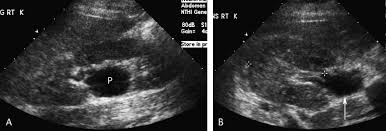

Kidney Stones Not Seen On Ultrasound. Ultrasound can be efficient in visualizing clear uric acid stones and obstructions caused by any type of kidney stones. Some kidney stones may not show on ultrasound if the stones are less than 3mm the ultrasound exam may not be able to detect in some cases cat scan.

Spiral ct scan is the most reliable imaging tool for small kidney stones. A counter argument for using ultrasound in diagnosing of kidney stones is that ureteral stones are usually difficult to visualize with ultrasound and unless they are located at upj or in the distal ureter will not be seen with ultrasound. Flank pain microscopic blood in urine are frequently good clues to presence of stones.